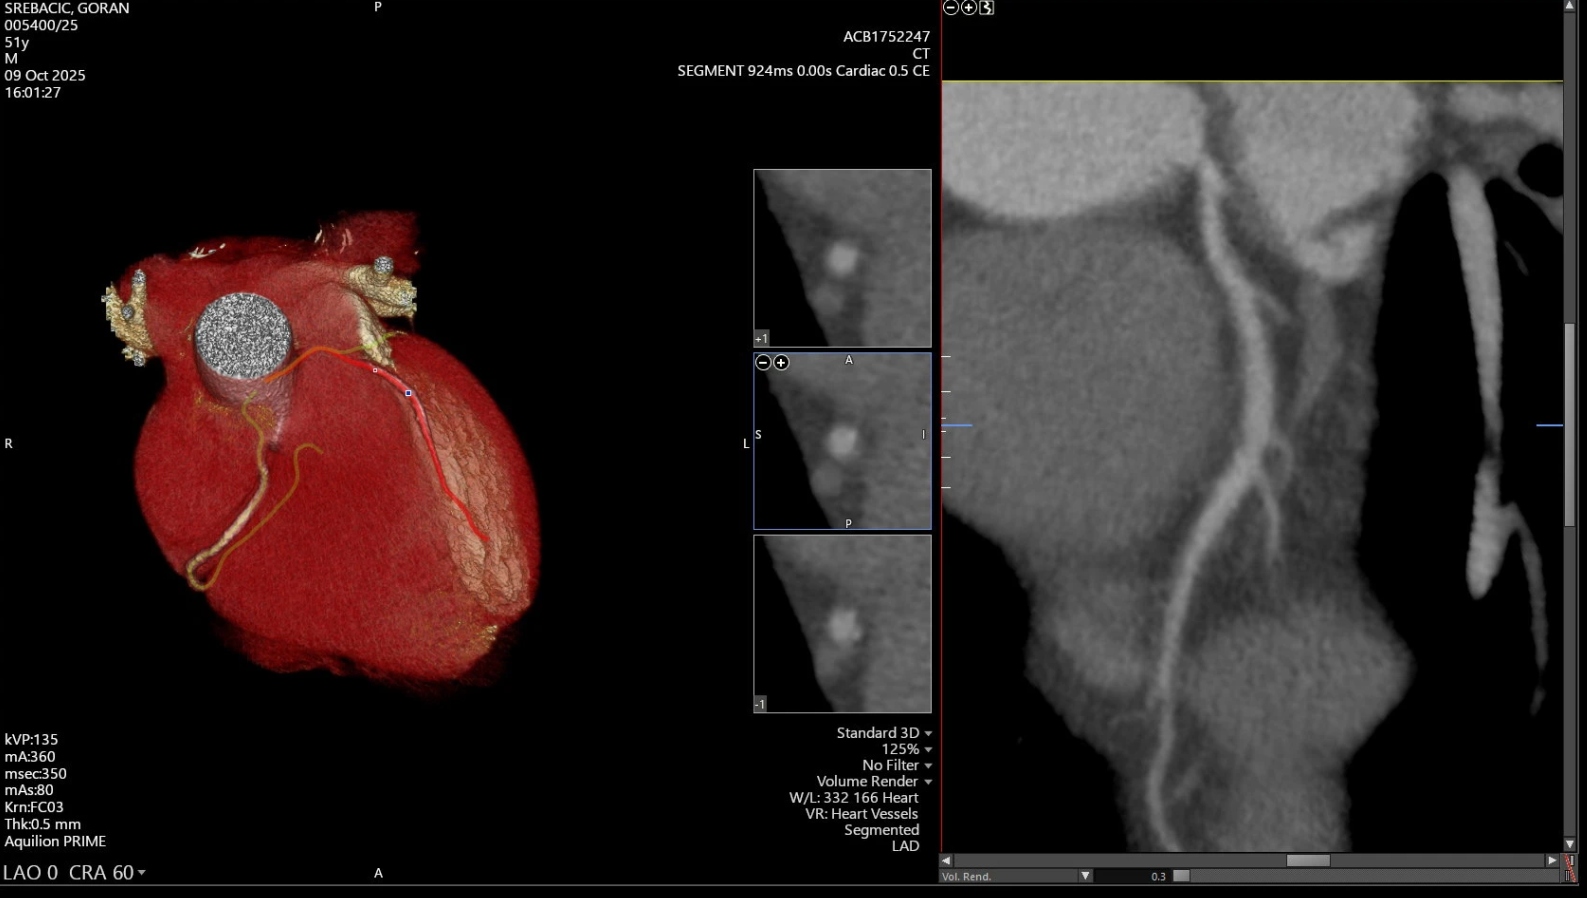

MSCT koronarografija je neinvazivna metoda prikaza srčanih arterija koja se danas smatra zlatnim standardom u ranom otkrivanju bolesti srca. Ova najmodernija radiološka pretraga omogućuje preciznu procjenu suženja i začepljenja koronarnih arterija bez potrebe za invazivnim zahvatom poput uvođenja katetera u krvne žile. Pretraga traje svega nekoliko minuta, a rezultati su izuzetno pouzdani.

Calcium scoring je probirna metoda kojom se mjeri količina kalcija u stjenkama krvnih žila. Budući da nakupljanje kalcija označava prisutnost ateroskleroze, ova pretraga omogućuje brzu procjenu kardiovaskularnog rizika, odnosno rizika od srčanog udara. Često se izvodi samostalno ili u kombinaciji s MSCT koronarografijom.

Dvoje pacijenata bez simptoma imalo kritično suženje arterije

„Nažalost, mnogi ljudi s navedenim rizičnim čimbenicima nemaju ikakve tegobe dok ne dožive srčani udar. MSCT koronarografija omogućuje nam da bolest otkrijemo na vrijeme – bezbolno i sigurno. Ova pretraga predstavlja vrhunac suvremene radiološke dijagnostike i iskreno smo ponosni što je možemo ponuditi našim sugrađanima. Dosadašnje snimke pokazale su iznimnu kvalitetu i preciznost. Kad smo tek uveli ovu pretragu, dvoje od prvih deset pacijenata, koji nisu imali nikakve simptome, imalo je kritično suženje koronarne arterije. Riječ je o osobama koje su bile u predinfarktnom stanju, a da toga nisu bile svjesne. Upravo takvi slučajevi pokazuju koliku vrijednost ima ova pretraga – ona doslovno spašava živote“, izjavio je dr. sc. Nikola Ivan Leder, ravnatelj Medicinskog centra Gorica.

Ove suvremene dijagnostičke metode omogućuju preciznu procjenu stanja koronarnih arterija i procjenu rizika od kardiovaskularnih bolesti — često i prije pojave prvih simptoma.